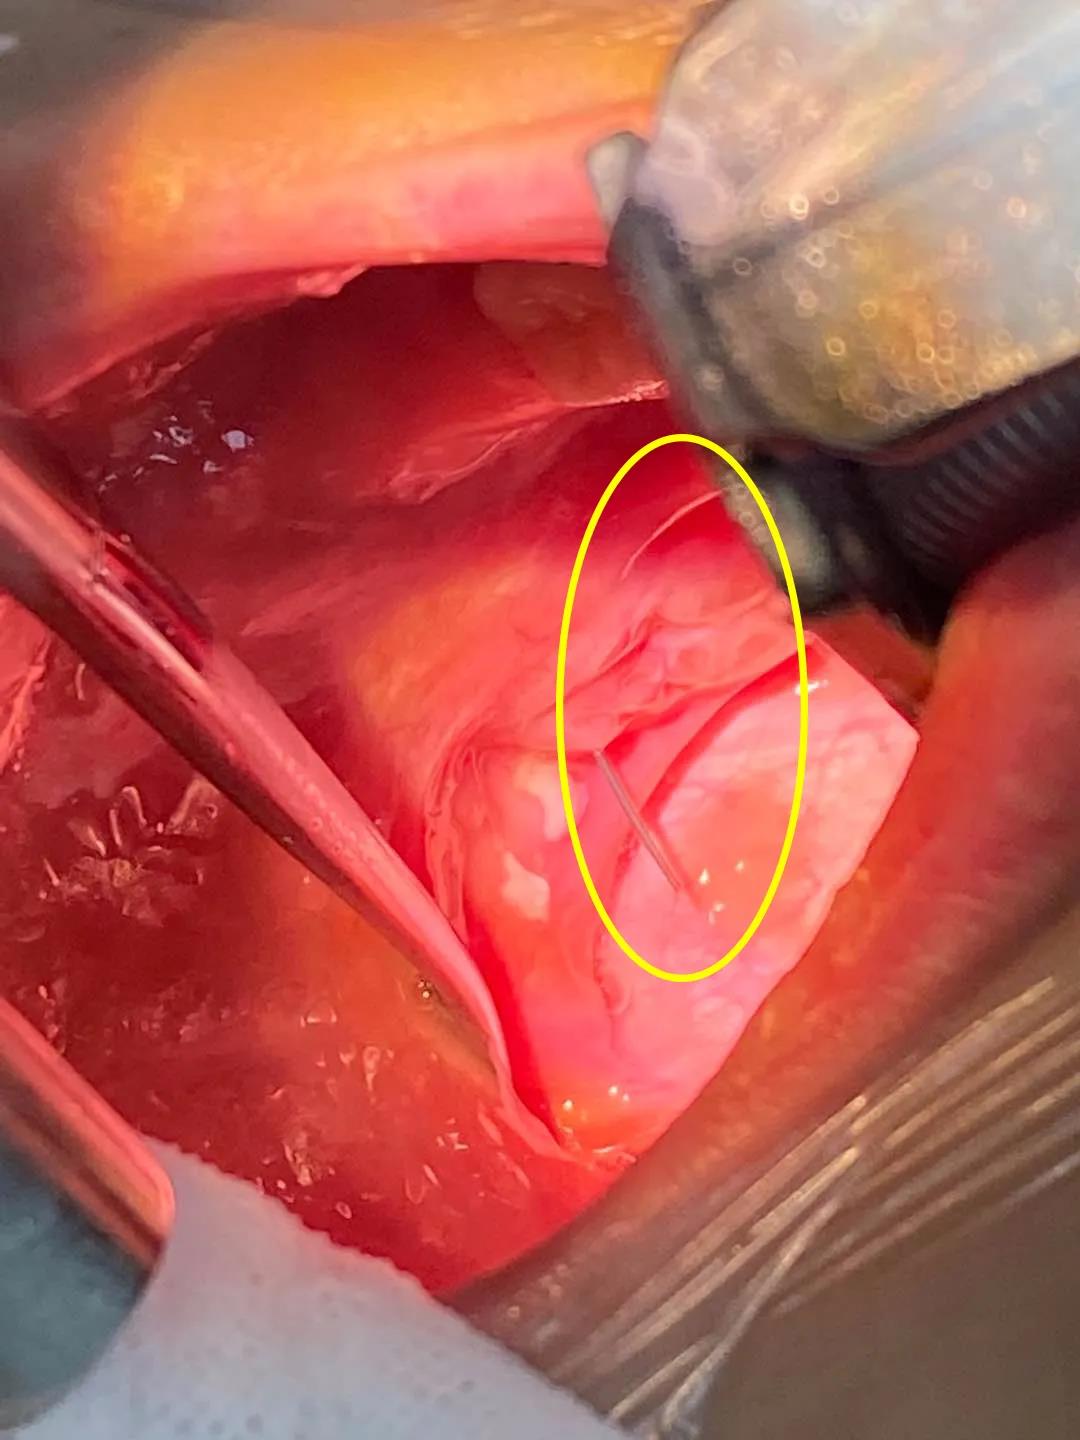

经咽喉部CT提示,一根弯弯的钢丝,牢牢地戳在了患童口咽上腭悬雍垂左侧。

3月28日下午,我院儿童耳鼻喉科马玉龙主任对金金实施了急诊手术,取出了这根困在口腔内20天、长达5厘米的钢丝。因戳入时间过长,有炎症表现,金金粘膜充血,左侧有白色假膜附着,悬雍垂后壁还有少许淋巴滤泡增生。